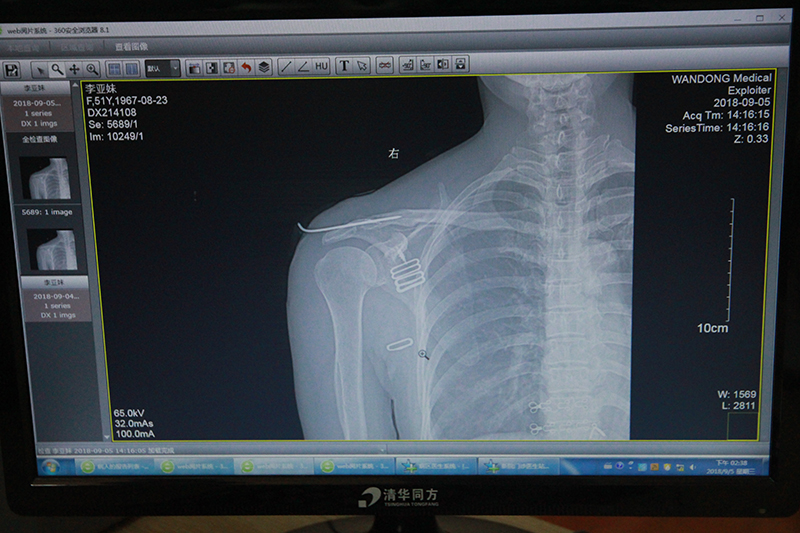

听出曹先生语气中的焦虑,主任鲍立峰查问得尤为细致详尽,“根据目前右肩的状况,想要不通过手术而恢复如初是不太可能的,不及时治疗反而会加重伤情。但是手术方案可以调整,通过肩锁钩钢板手术治疗的话,之后不需要进行二次手术,而且这项手术属于微创手术,创伤小,恢复也快,术后功能锻炼不会太痛苦。”

术后